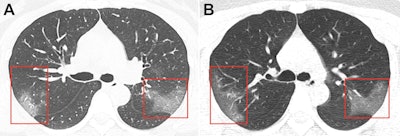

Unenhanced chest CT scans of the patient showed multiple peripheral ground-glass opacities in both of her lungs, and subsequent DNA tests were positive for 2019-nCoV. CT scans acquired three days after treatment revealed progressive pulmonary opacities, indicating that the patient's condition was worsening despite treatment.

Chest images, in conjunction with epidemiologic characteristics and laboratory tests, were critical in diagnosing coronavirus-infected pneumonia in this patient and also monitoring disease progression, Lei and colleagues noted.